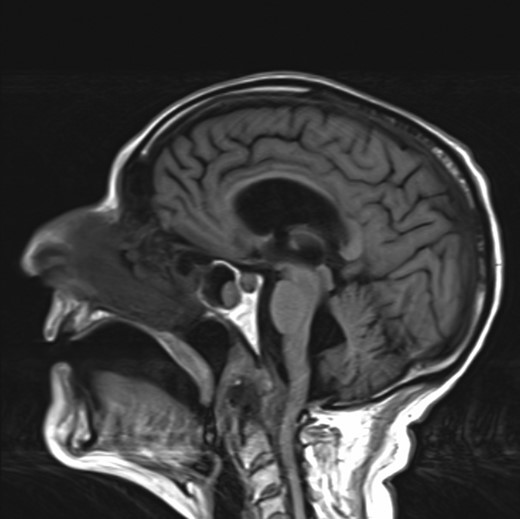

Due to crowding of his foramen magnum, a decision was made to have a MRI head and spine. This showed erosion of the odontoid with marked degenerative changes at the atlantodental joint. Interestingly, a large tissue mass presumed to be a pannus was also seen causing severe compression at the cervico-medullary junction and obstruction to CSF flow at this level (Fig. 2). Prior to this presentation, the patient had never suffered from any neck pain or limb weakness.

MRI head showing a large tissue mass and erosion of the odontoid causing CSF outflow obstruction at the cervico-medullary junction.